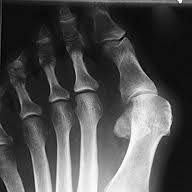

Diagnosen

Normalt røntgenbildeDiagnosen stilles på grunnlag av de typiske funnene. Røntgen kan utelukke leddbetennelse og vise eventuelle slitasjeforandringer i tåens grunnledd. Vanligvis er det unødvendig å ta røntgen for å stille diagnosen, men røntgenbilder er nyttige for kirurgen i forberedelsene til en operasjon.

Stortåen er vridd utover (valgisert) 15-20°. Blir valgusstillingen mer enn 20°, vil trekk i det indre stortåbeinet (grunnfalangen) via bøye- og strekkesener ytterligere forsterke stortåens tendens til skjevstilling (valgisering). Grunnleddet vil bli presset ut og trykk fra sko vil medføre en kronisk irritasjon av en slimpose (bursa) som ligger utenpå grunnleddet. Med tiden vil det dannes en beinet utvekst (eksostose) i grunnleddet, noe som ytterligere forsterker trykkplagene. Stortåens "vandring" vil også påvirke de nærmeste tærne, som kan innta en mer eller mindre uttalt hammertåstilling.